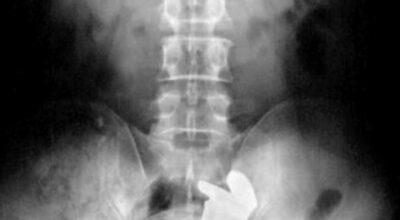

Esta recopilación de imágenes recoge alguna de las situaciones más estrambóticas que se han podido dar en una sala de rayos X. Todas ellas tienen algo en común: Son objetos extraños para el cuerpo humano que, de alguna manera han encontrado una vía de entrada, pero se han perdido a la hora de encontrar la de salida.

Muñecas de juguete descabezadas, botellas, armas, frascos, botes de plástico, teléfonos y hasta una cinta de casete pueden encontrarse en esa suerte de “punto limpio” al que ha quedado reducido el interior de los afectados.